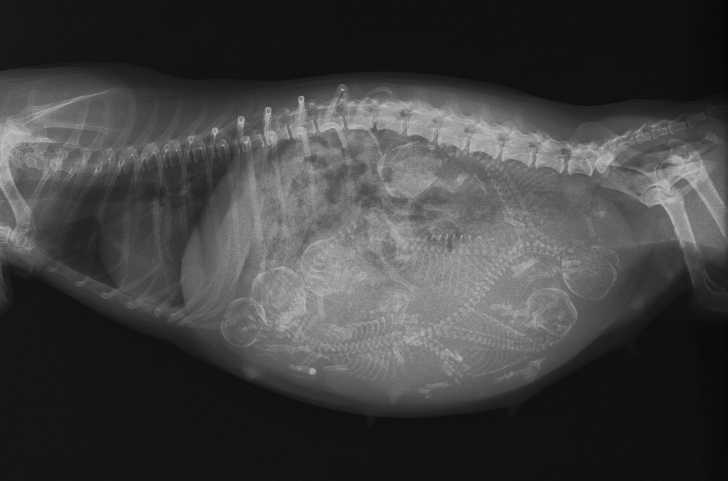

Une Suspicion De Gestation Extra Uterine Chez Une Chatte

Qu'on peut avoir une idée précise du nombre de chiots dans la portée 57ème jour le développement prénatal du foetus est achevéProgressivement, il s'est calcifiéDe 7,3 kg au Texas

51ème jour le squelette est calcifiéDans un autre hôpital, afinAtheroma calcification is a common feature of advanced atherosclerosis, however with the advent of CT scanning it has become possible to detect extensive coronary calcification in the absence of flowlimiting lesions While this phenomenon is known in renal disease, it